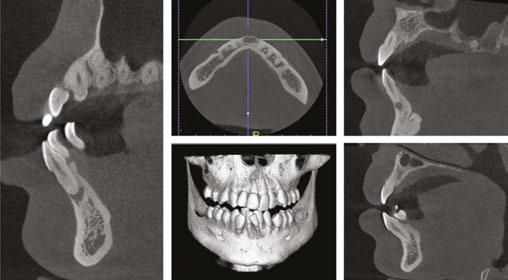

Radiographic evaluation

It was clear that extractions were going to be necessary to relieve crowding for this patient. It was unclear which mandibular teeth would be best suited for extraction, considering that tooth Nos. 24, 26, and 27 were ectopic and considerably displaced out from the center of the alveolar housing or trough (Figure 2B). Additionally, tooth No. 24 was already showing signs of gingival recession (Figure 2D), further suggesting its position within the alveolar housing was compromised.

A CBCT X-ray was captured to further investigate and compare which mandibular anterior teeth were most compromised, as well as better visualize any pathologies that may be present (when compared to a panoramic X-ray, Figure 3). When visualizing individual teeth, crosshairs in the 3D imaging software were centered in each orthogonal direction to ensure image accuracy and reproducibility. The image is adjusted to view all teeth either parallel or perpendicular to its axis making sure that the evaluations are accurate in comparing each tooth and its supporting bone.

The CBCT image revealed several findings. First, it was apparent that a periapical radiolucency (PARL) existed in association with the overlapping mandibular incisors (Figures 4A – 4C). Figure 4A shows tooth No. 24 with compromised facial alveolar support, while figure 4C shows tooth No. 25 with a greater amount of visible facial bone. In figure 4E, tooth No. 27 is proclined and has compromised facial alveolar support. Lastly, a second PARL was noted surrounding tooth No. 8 (Figure 5).

Treatment plan

The established treatment plan and extraction recommendation for this patient was primarily based on the CBCT image findings with regards to alveolar support and space analysis. It was clear that tooth No. 24 had the least alveolar support and was already experiencing gingival stripping. However, extraction of this tooth alone would not provide enough space to relieve the crowding, as it is already entirely blocked out of the arch. If one were to extract tooth No. 28 also, tooth No. 27 would need to be distalized and retracted into the arch to allow room for the alignment of the remaining incisors. A potentially more efficient plan would be to extract the periodontally compromised tooth No. 27, as its root is already significantly dehisced thru the facial cortical plate making room for proper alignment of tooth No. 26. Therefore, the final treatment plan for this patient is as follows: refer to general dentist or endodontist for evaluation of PARLs on tooth No. 8 and No. 25 (Figures 4A, 5A, and 5B) and extraction of Tooth Nos. 5, 12, 24, and 27 (Figures 6A and 6B).

Figure 3: Panoramic X-ray taken with diagnostic records on December 17, 2020 Figures 5A-5B: 5A. Shows the sagittal view of tooth No. 8 with associated PARL. 5B. Shows the coronal view of tooth No. 8 with associated PARL Figures 6A-6B: 6A. Shows extractions of tooth Nos. 5 and 12. 6B. Shows extractions of tooth Nos. 24 and 27 Figures 4A-4D: 4A. Shows the sagittal view of tooth No. 24 with what appeared to be an associated PARL. Figure 4B shows the PARL from an axial view centered in the mandibular anterior region. Figure 4C shows tooth No. 25 in the sagittal view, closely associated with the PARL. Figure 4D shows the 3D model of the maxillary and mandibular arches. Figure 4E shows tooth No. 27 in the sagittal view A. B. D. C. E. A. A. B. B.